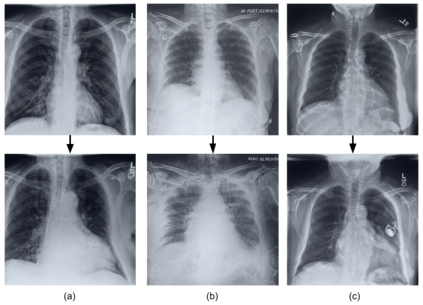

Deep learning models used in medical image analysis are prone to raising reliability concerns due to their black-box nature. To shed light on these black-box models, previous works predominantly focus on identifying the contribution of input features to the diagnosis, i.e., feature attribution. In this work, we explore counterfactual explanations to identify what patterns the models rely on for diagnosis. Specifically, we investigate the effect of changing features within chest X-rays on the classifier's output to understand its decision mechanism. We leverage a StyleGAN-based approach (StyleEx) to create counterfactual explanations for chest X-rays by manipulating specific latent directions in their latent space. In addition, we propose EigenFind to significantly reduce the computation time of generated explanations. We clinically evaluate the relevancy of our counterfactual explanations with the help of radiologists. Our code is publicly available.